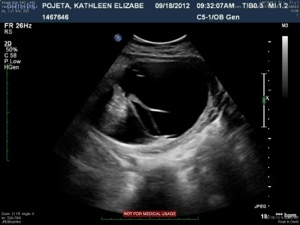

Here is a profile of our little Colten…

20120921-213454.jpg

This image shows the bottom portion of the spine (lumbar and sacral). The large black area surrounded by a jelly-bean type shaped white line is the cyst, or sac.